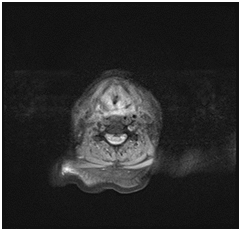

A 70 years old male patient presented to the emergency department with stridor and dysphagia of 3months duration. Patient was examined by fiber optic nasopharyngoscope which revealed supra-glottic mass to the left side with restricted mobility of the left vocal cord. Patient was admitted and submitted for urgent tracheostomy. MRI neck with contrast was done and revealed a Supraglottic mass measuring about 2cm X 1.5cm, partially occluding the airway and showing enhancement post gadolinium injection. It is appearing isointense in T1 and T2-weighted images with mildly enlarged vocal cords (Figure 1–3).  Panendoscopy was performed on 18/02/2018 and revealed a mass occupying the post cricoid area, pyriform fossa, supraglottic and the lateral pharyngeal wall. Base of the tongue, tonsils, right side of the larynx and the posterior pharyngeal wall were free.

Figure 1 MRI neck with contrast, axial cut showing supraglottic mass lesion partially occluding the airway.

Figure 2 MRI neck, axial cut, showing supraglottic mass lesion partially occluding the airway.